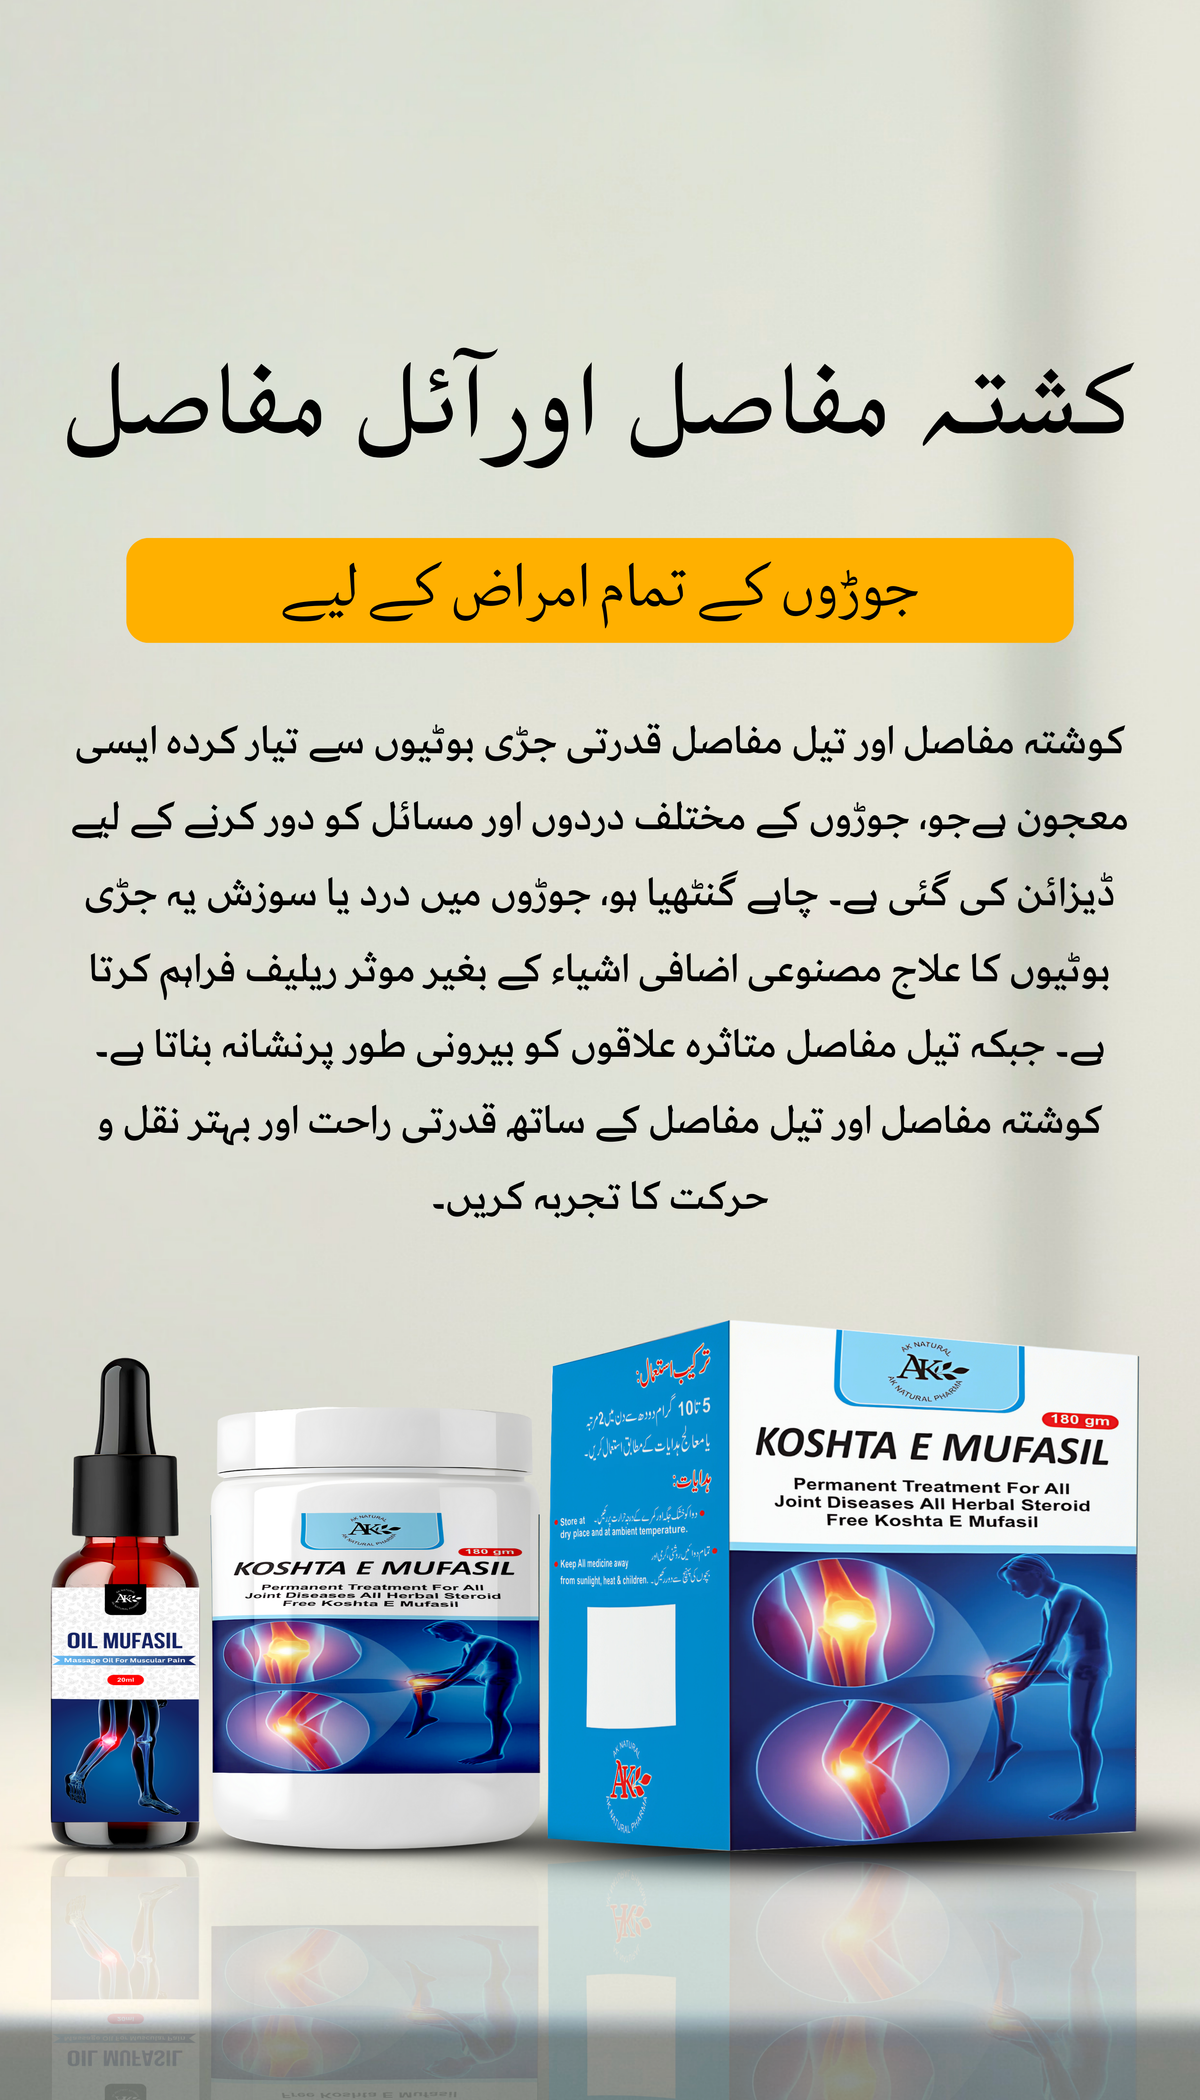

KOSHTA MUFASIL & OIL MUFASIL

میری دادی کو جوڑوں کا درد تھا جس کی وجہ سے ان کو راحت نہیں ملتی تھی۔ کوشتہ مفاصل اور تیل مفاصل نے ان کو بہتر بنایا

جب سے میں نے کوشتہ مفاصل اور تیل مفاسل کا استعمال شروع کیا ہے، میں نے اپنی مشترکہ نقل و حرکت میں غیر معمولی بہتری کا تجربہ کیا ہے۔

How do Koshta Mufasil and Oil Mufasil work?

Koshta Mufasil is an herbal supplement taken orally, while Oil Mufasil is a topical oil applied directly to the affected joints. Both products work synergistically to reduce inflammation, relieve pain, and improve joint mobility.

How quickly can I expect to see results with Koshta Mufasil and Oil Mufasil?

Results may vary depending on individual factors such as the severity of joint pain and overall health. Some users may experience relief within days of starting the regimen, while others may require several weeks of consistent use. Patience and adherence to recommended usage guidelines are key.